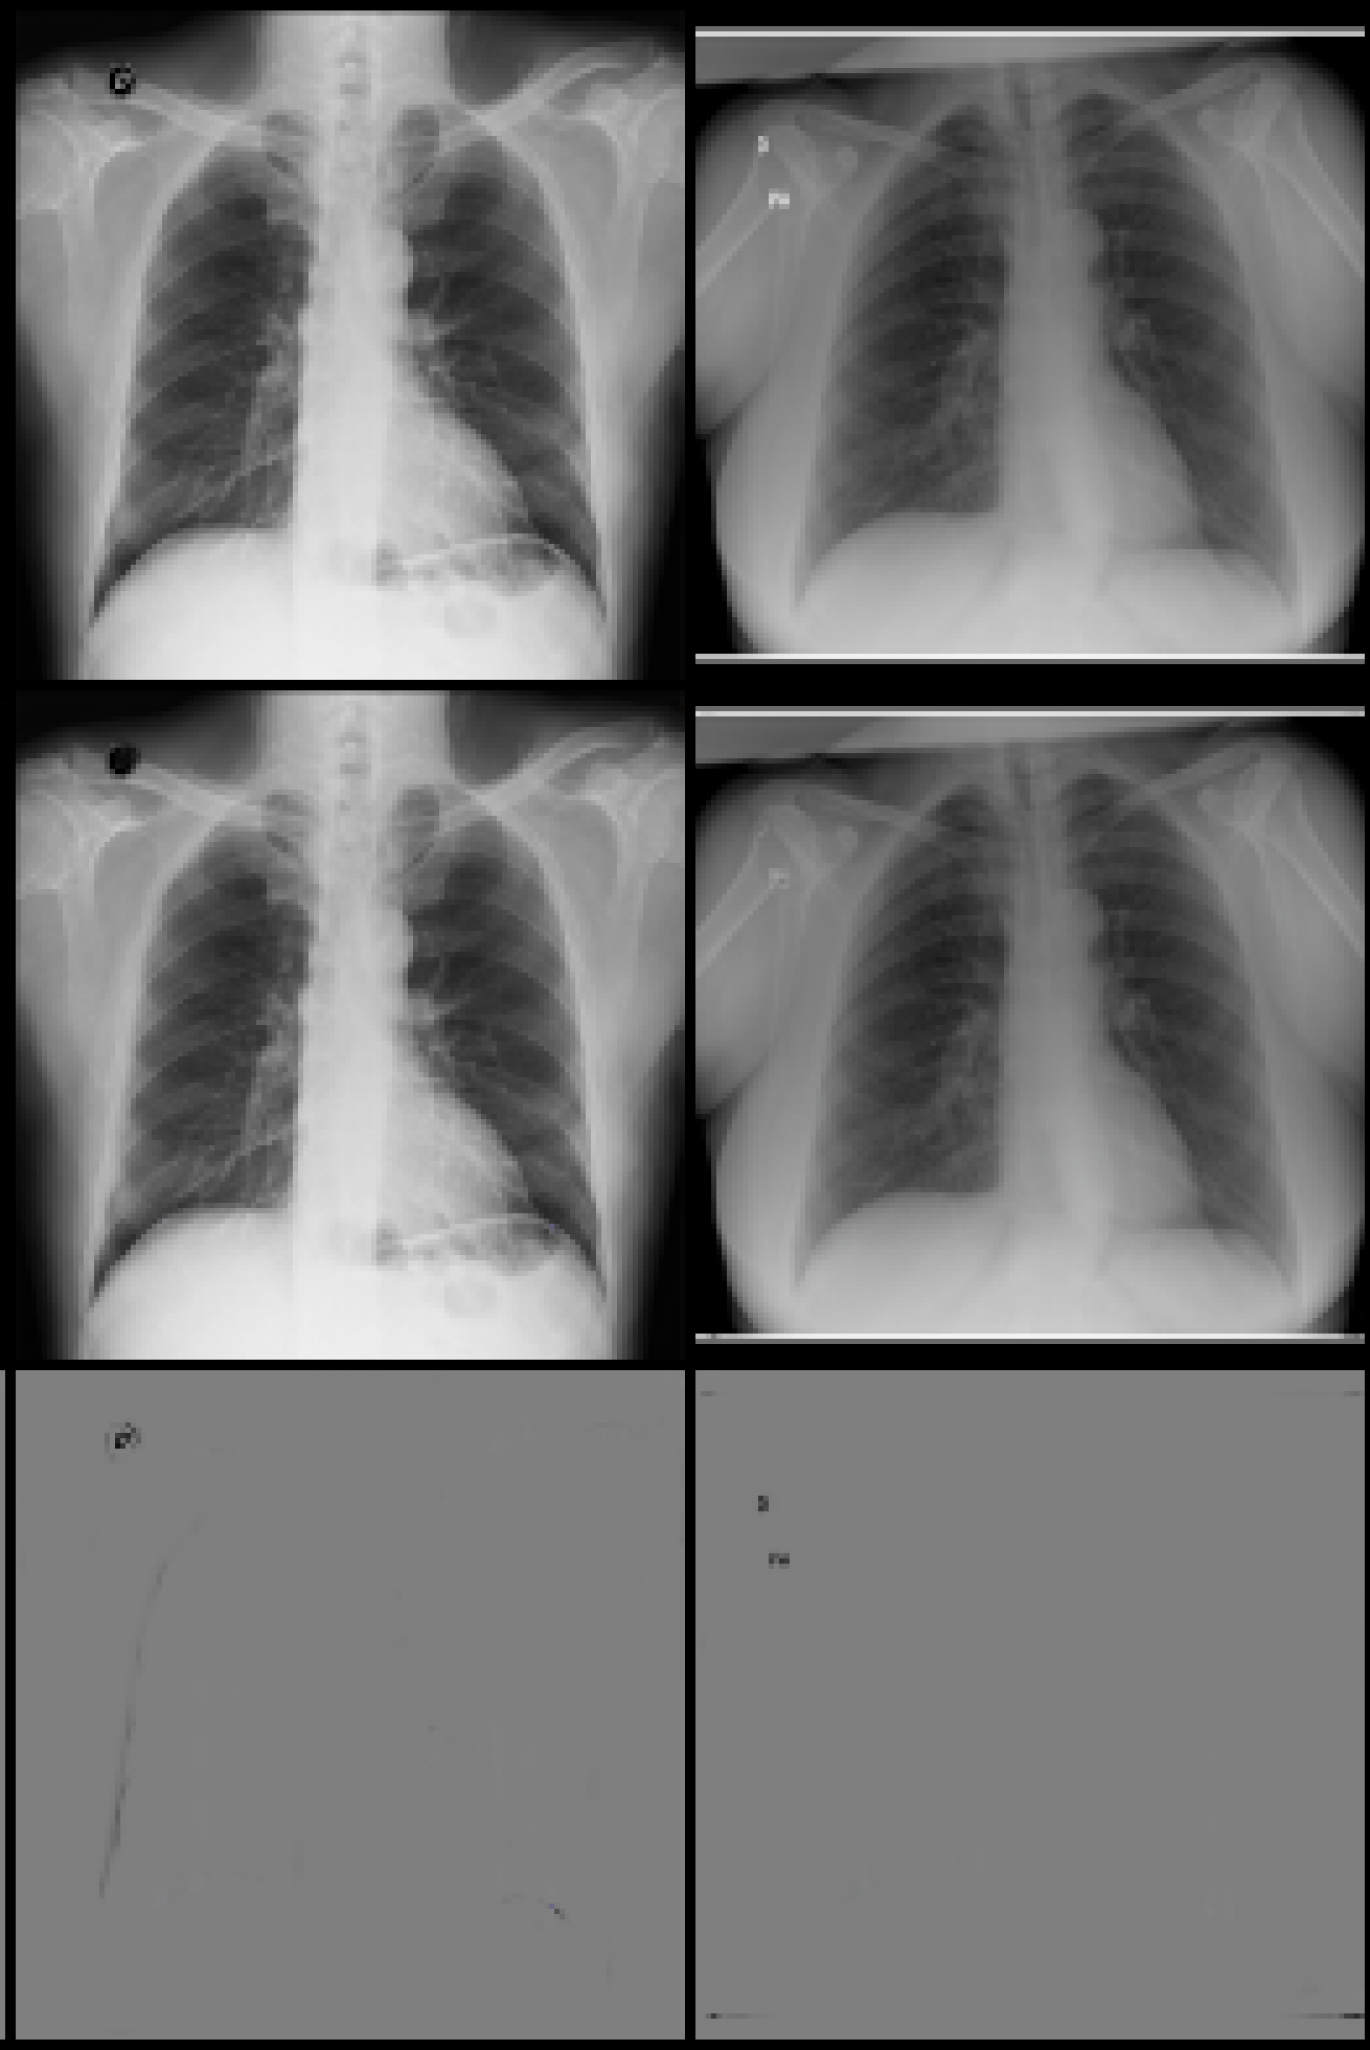

Original Lense output Difference

Refer to caption

(a) Normal

(b) COVID

Figure 5: Lens output and attention on x-ray images from the covid-qu-Ex dataset for the classes classes COVID and Normal. Row 1 shows original images. Row 2 shows the output of the lens. Row 3 shows the difference between rows 1 and 2.